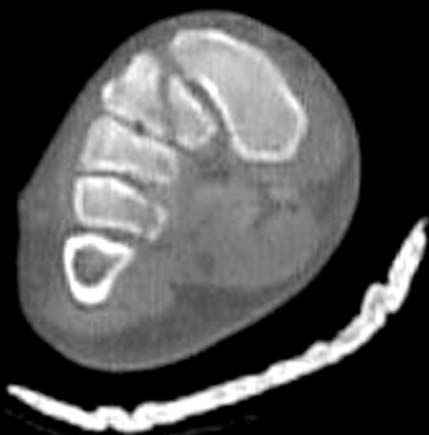

Здесь КТ и сравнительные снимки стопы под нагрузкой.

Диагностировано повреждение медиальной и латеральной колонны.